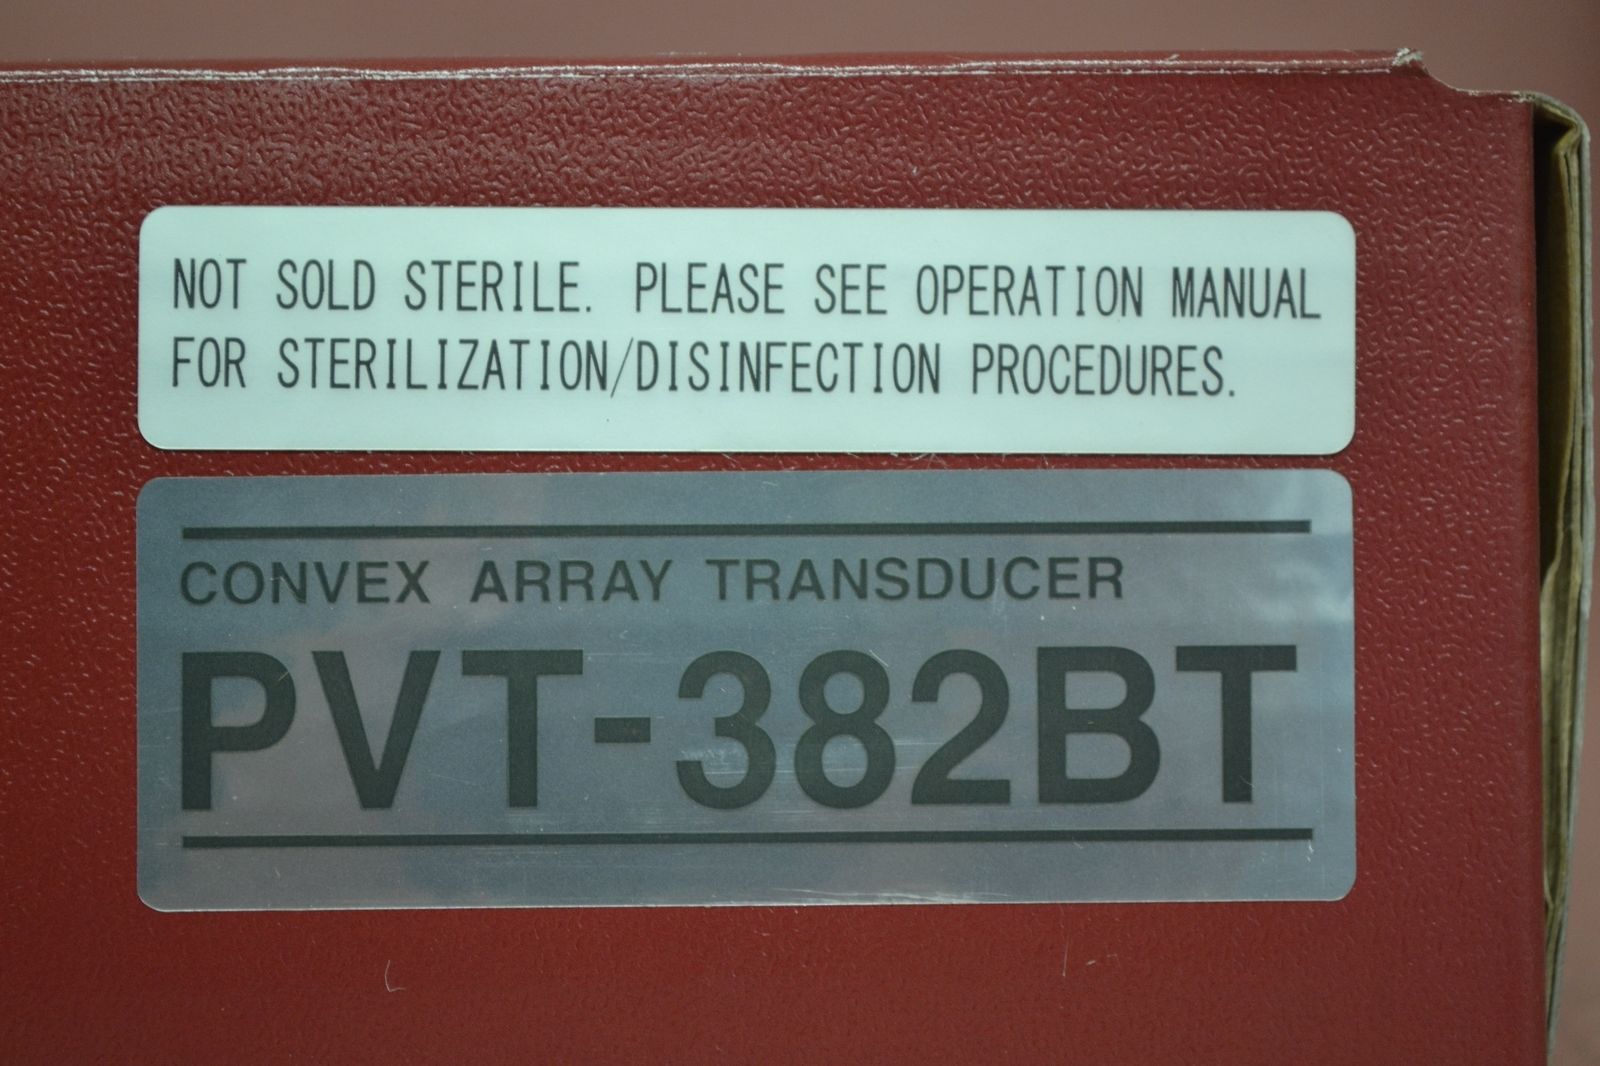

Toshiba Probes

DIAGNOSTIC ULTRASOUND MACHINES FOR SALE